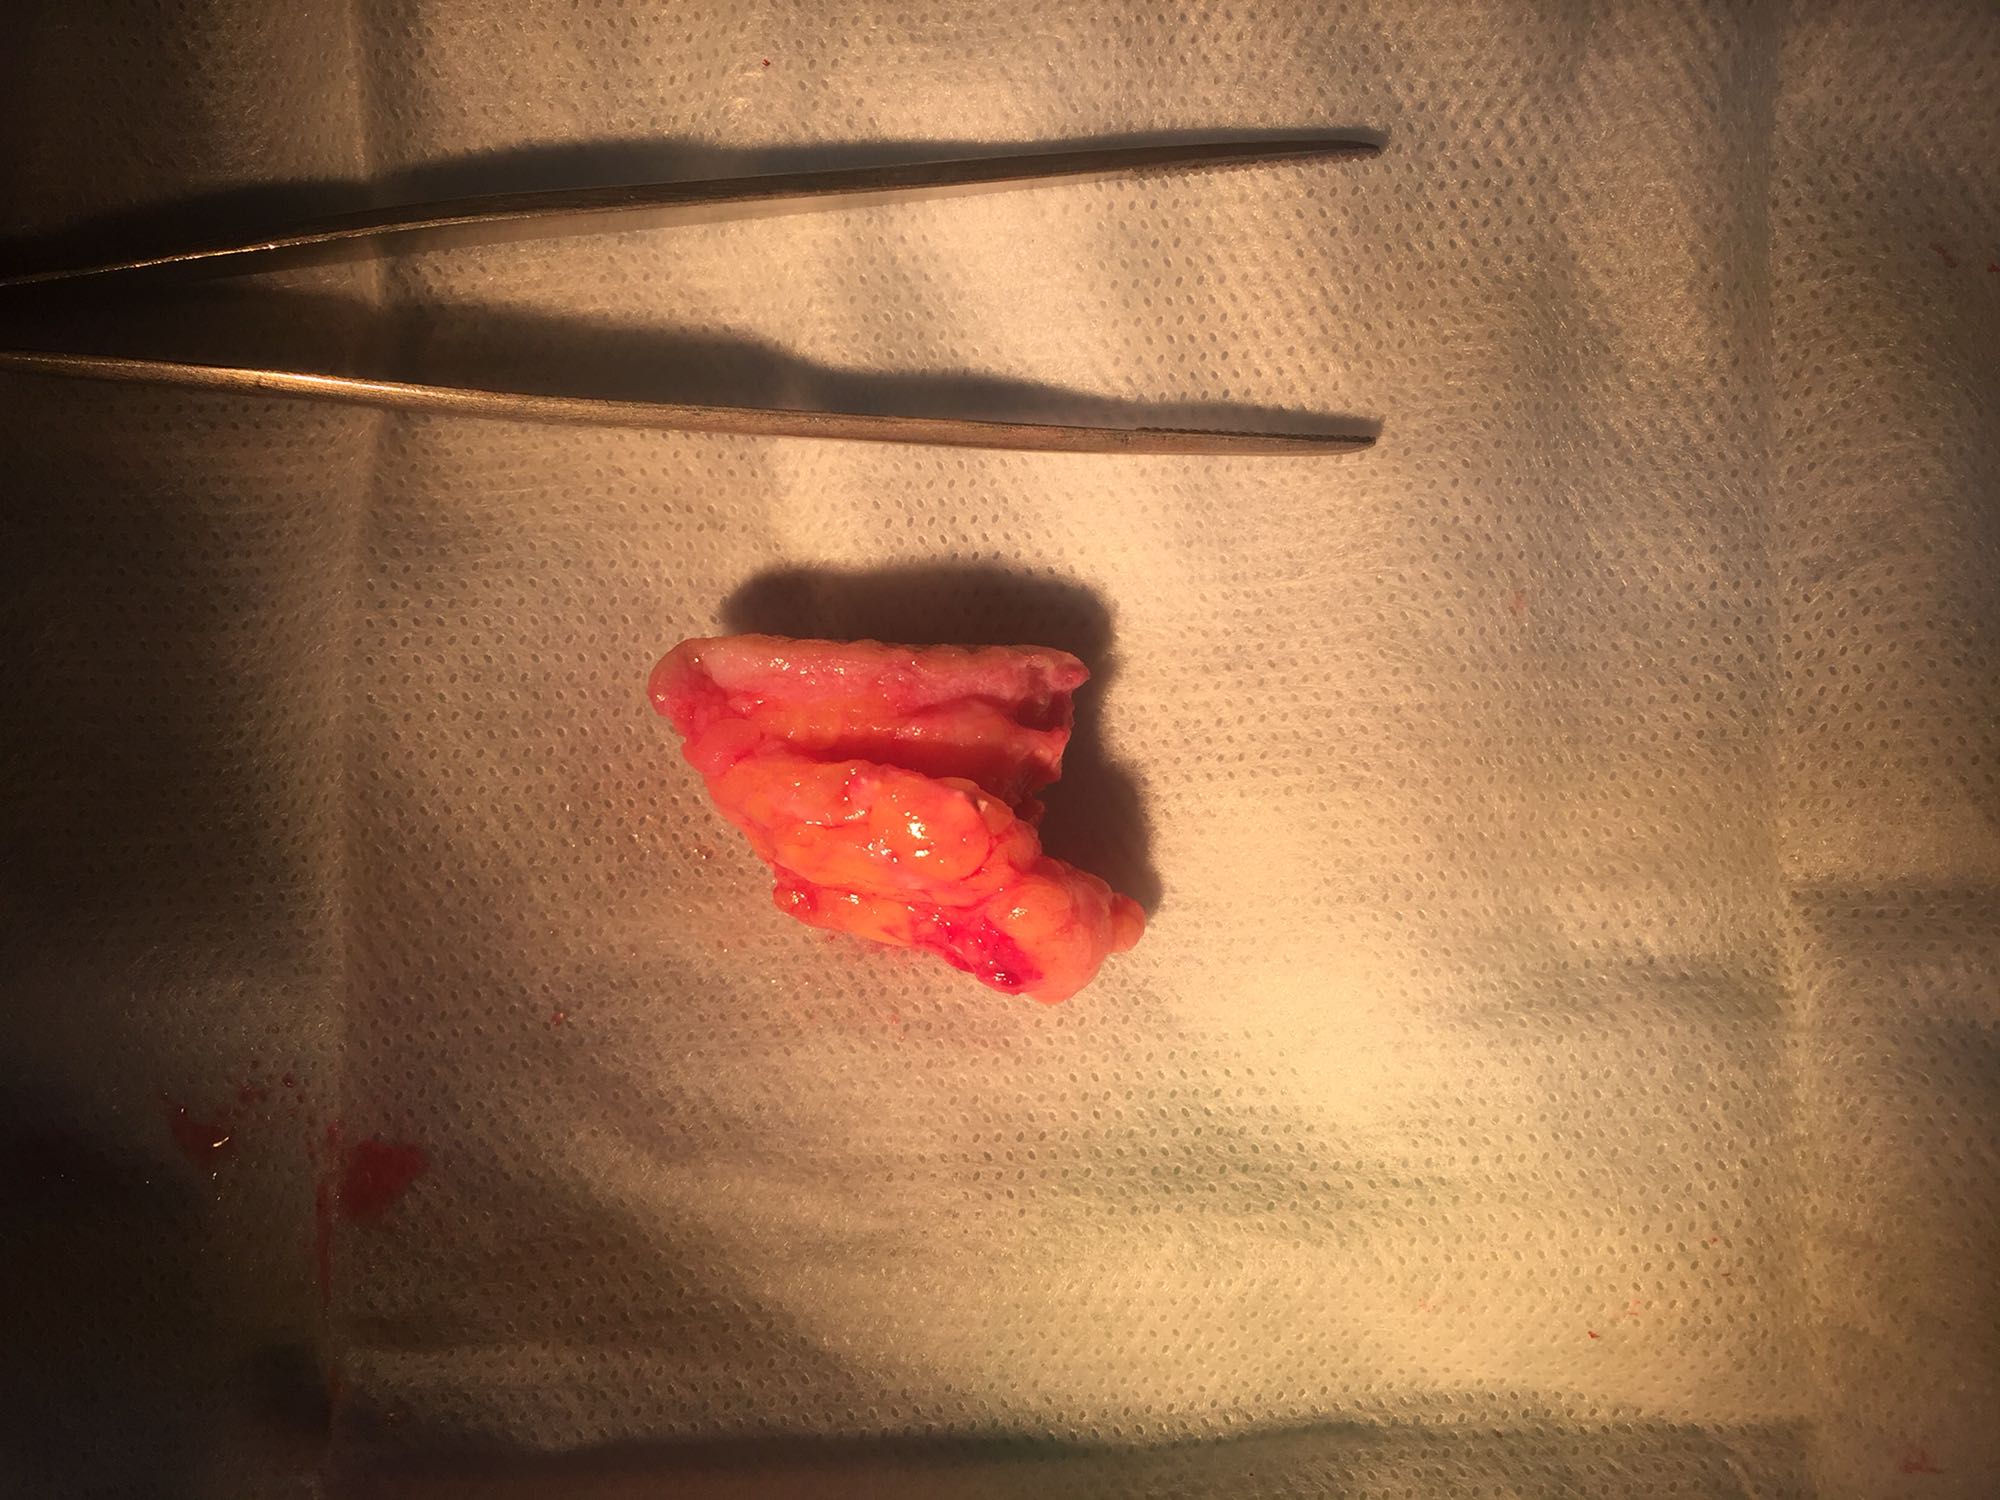

诊断:左侧大腿皮下肿物。 治疗:局麻下行左侧大腿皮下肿物切除手术,术中见肿物不规则,约4*3*3cm大小,质地不均匀,内有多个骨骼样肿物,无包膜。术后病理:钙盐沉积伴慢性炎症。